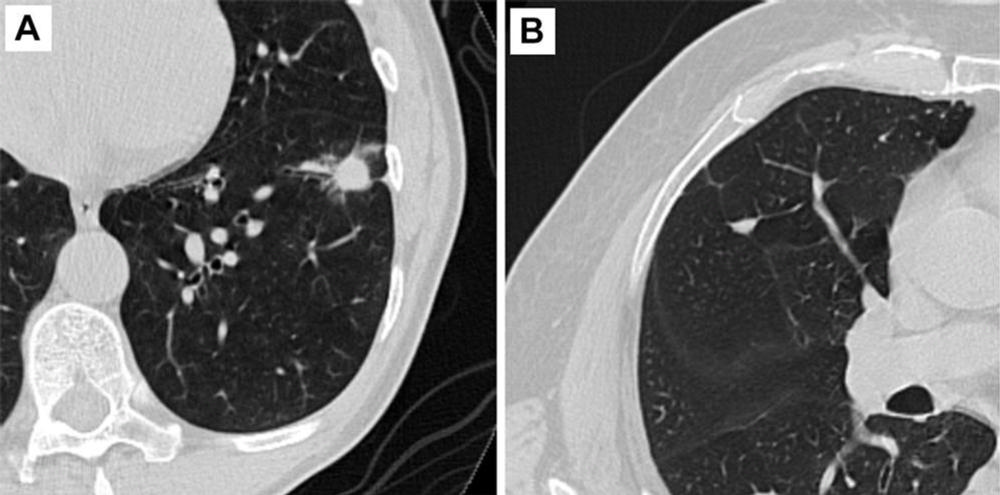

Figure 2. Axial CT images of pulmonary nodules. (A) Malignant nodule. (B) Benign nodule.